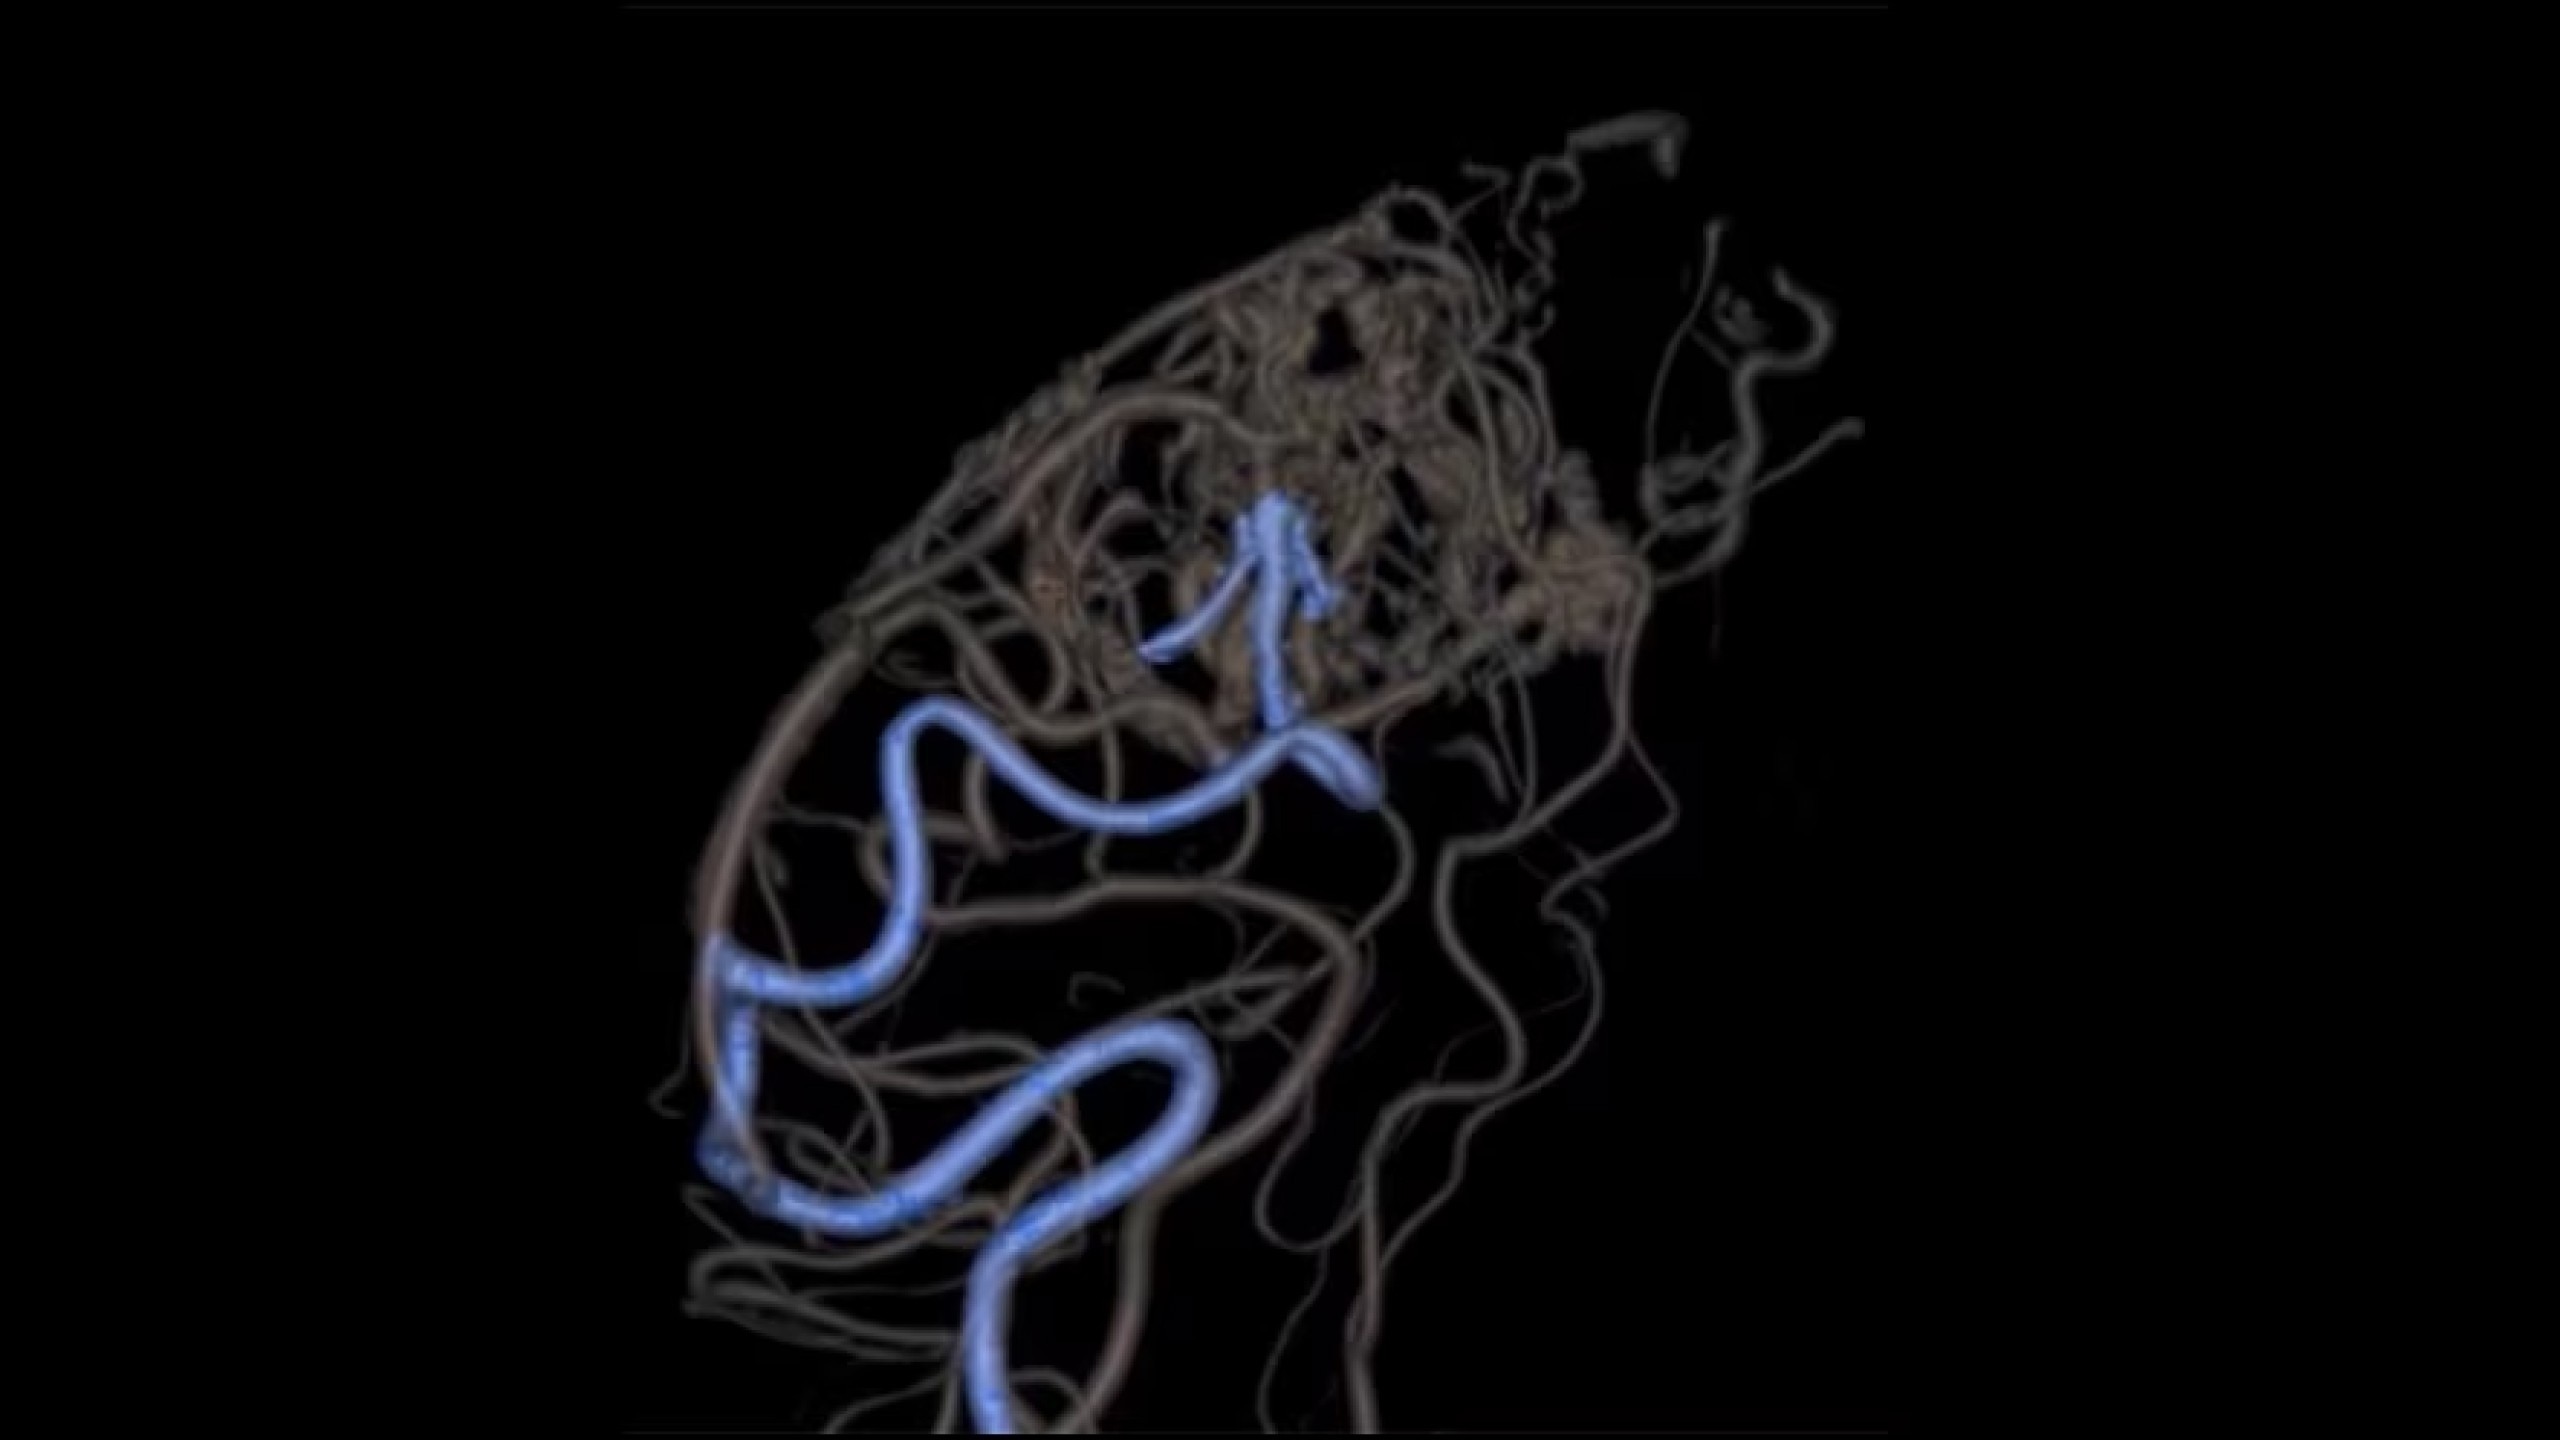

Embo ASSIST is an AI-based augmented guidance solution designed to define optimal embolization strategies and streamline your clinical workflow.

Segment vasculature from CBCT in one click

Visualize multiple vessels and navigate in cross sections to facilitate planning

See the unseen with Vessel ASSIST